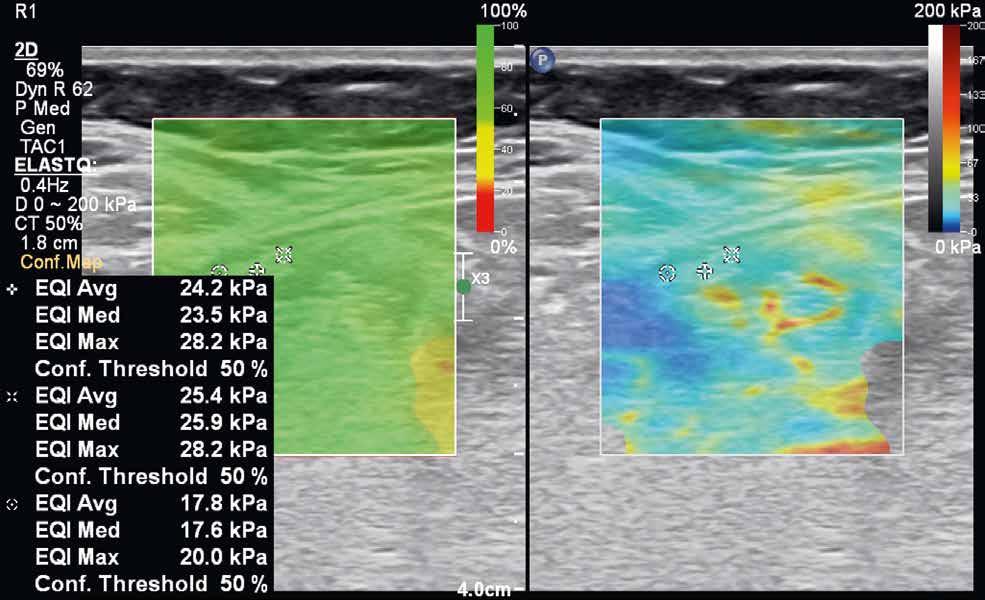

rychlost na hodnoty tlaku v kilopascalech. Výsledná informace je opět kódována do barevné mapy (v klasickém B-obraze), zachycující škálu tuhosti vyšetřované tkáně. Tranzientní elastografie využívá k vyslání pulzu mechanických vibrací sondy, bodová shear-wave elastografie využívá výše popisovanou techniku ARFI ke generování pulzu do jednoho bodu. Nevýhodou tranzientní elastografie je absence klasického B-módu, a tedy nemožnost morfologického zhodnocení vyšetřované tkáně. Nejnovější technikou je 2D shear-wave elastografie (obr. 4–7). Iniciálně je v krátkém časovém intervalu vysláno několik akustických pulzů, následovaných vznikem střihových vln ve více bodech. Výhodou této techniky je možnost sledovat tuhost tkáně v reálném čase. Některé moderní přístroje využívající 2D shear-wave elastografii mají nástroj označovaný „confidence map“. Mapa se zobrazí ve druhém okně na displeji přístroje a pomocí barevné škály hodnotí úroveň, s jakou se v daném místě propagují střihové vlny. Na základě těchto informací pak může vyšetřující zvolit optimální místo k měření tuhosti tkáně.

Obr. 4–7: Elastografie. U pacienta s Crohnovou nemocí ve fázi aktivního zánětu vidíme edematózní stěnu s prosáknutím a uzlinami v okolí (5). Elastograficky je stěna „měkčí“ (4) ve srovnání s pacientem s chronickou fází onemocnění (6, 7), u kterého je stěna fibrózně změněná.